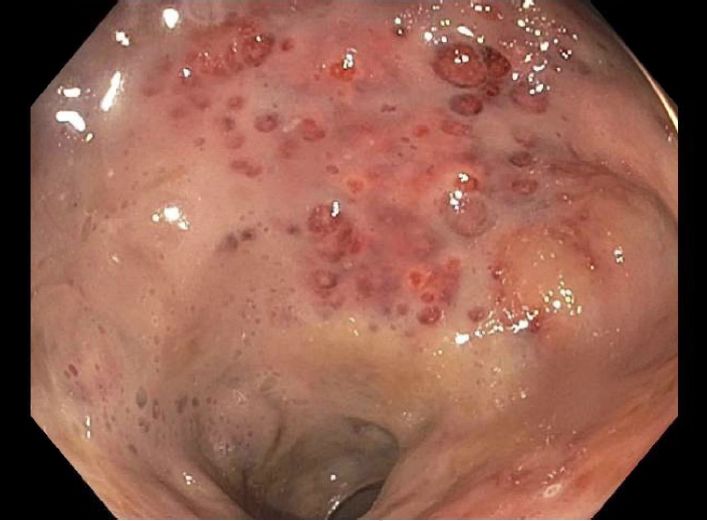

HIV和粪便检查结果为阴性。腹部和骨盆的计算机断层扫描(CT)扫描提示了异常发现(图A,图B),因此,我们又用内窥镜对患者进行了检查。在接下来的几天,乙状结肠镜检查的结果如图C、图D和图E。

图C

腹部和骨盆的CT显示直肠壁增厚,提示直肠的炎症和充血,即直肠炎(图A,B)。乙状结肠镜检查的结果显示直肠和远端乙状结肠内的粘膜严重充血,伴随弥漫性红点(图C,D)与表面渗出物,且直肠和乙状结肠远端的粘膜脆弱。这些发现与化学直肠炎,特别是过氧化氢诱导的化学直肠炎的表现一致。

即使在化学性直肠炎中,由过氧化氢引发的化学性直肠炎也并不常见。 白色的渗出物(图E)和气囊(图C,D)是经典征象,被称为“白雪”标志,这种标志在同样的化学性直肠炎的病例中被多次发现与讨论。它的发病机制被认为是化学物质进入粘膜后,在损坏粘膜的同时形成氧气,故可见微泡的存在。